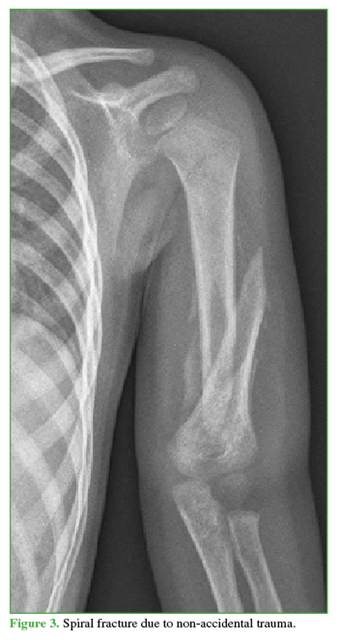

6.     Supracondylar humeral fractures in children are typically associated with accidental injuries, whereas the most common humeral fractures due to abuse in children <5 years of age are spiral or oblique fractures (Figure 3).